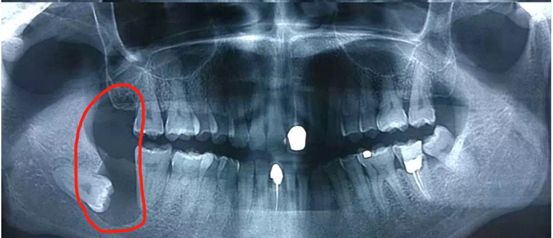

02.拍牙片

看不见的不等于不存在,也有可能是埋伏了。

看牙片就能清晰看到有没有智齿,智齿长的位置怎么样,要不要拔,一切清晰明了

如果发现长智齿了先淡定,让牙医来检查一下是不是阻生智齿,是不是什么问题都没有,如果确实都没有,那么不用拔。

以上是阻生智齿

但是其实80%都有问题的,最好还是拔掉。 因为不管长得正或不正的智齿,由于它身处口腔最深处,临近喉咙,给它的日常清洁工作带来了很大难度,刷不净,甚至根本刷不到,所以很容易发生蛀牙,智齿发炎痛起来也是很要命的~

智齿可以引起颌骨的萌出性囊肿,破坏颌骨,严重情况下可能需要截骨。这是会毁容的。所以,千万不要嘴里直视没看到智齿,也不疼不痒,就以为万事大吉。